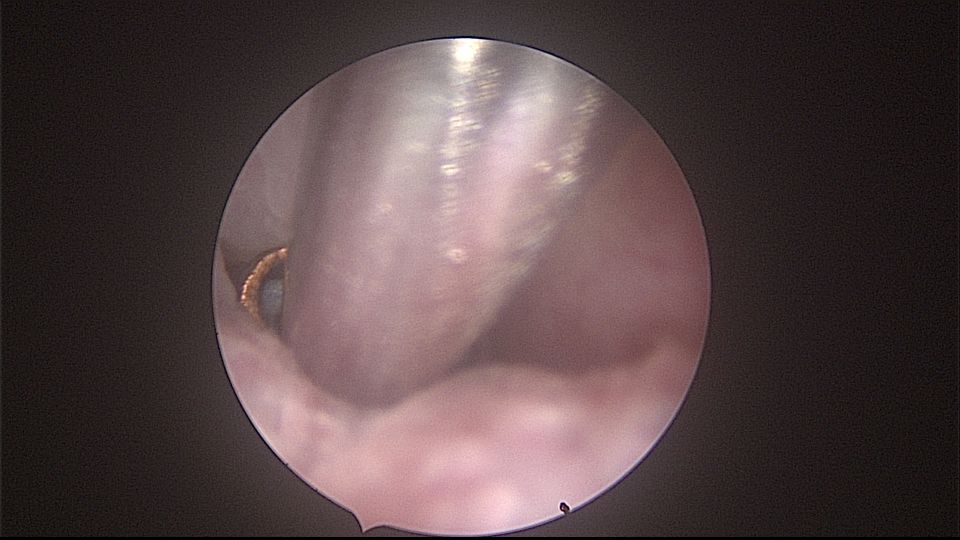

患者52岁,G2P1,顺产1次。安环27年,外院取环失败。病人肥胖,子宫极度前倾前屈位,宫腔镜见宫颈管组织杂乱,宫颈管上段右前壁见假道,膨宫不良,视野模糊,寻找宫腔方向困难,准备B超监护过程中,拆走扩阴器,腹部下压子宫,终于寻找到了宫颈内口,看到了爱母环下端,异物钳牵拉出节育环,再次探查宫腔,无其他异常。